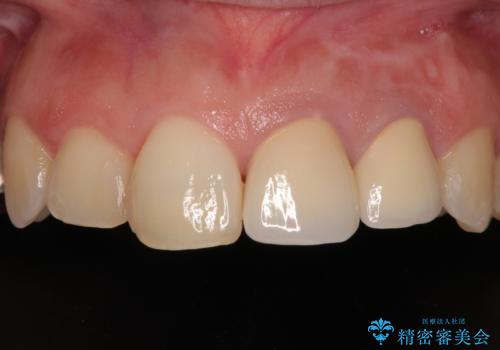

変色してきた歯とプラスチックのクラウン オールセラミッククラウン治療